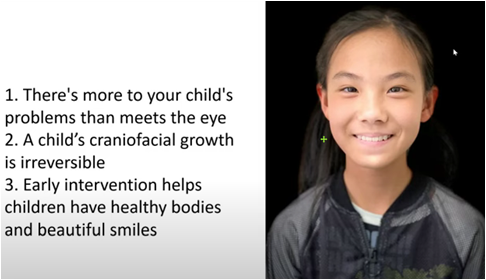

1. Why early correction is needed

There are many causes of malocclusion in early childhood. Heredity is usually the main cause. Other causes include trauma to the teeth, premature loss of deciduous teeth, and some bad oral habits (such as finger sucking, nail biting, lip biting, and tongue sticking out). Some mixed teeth Malocclusion in the orthodontic period can be treated early. The benefits of early treatment are to get rid of bad oral habits early, improve the appearance of the child, guide the permanent teeth to grow in the correct position, avoid the need for tooth extraction for correction in the future, or reduce the difficulty of correction in the future.

For children with malocclusion or abnormal bones

Orthodontic intervention must be dealt with in a timely manner. However, many parents do not know that bad habits such as mouth breathing and improper tongue positioning are also the main causes of children's irregular teeth. For example, "open bite" is mainly caused by children's bad habits. evolved.

In addition to the common traditional correction and Invisalign for children, MRC muscle function correction is also an option for early correction treatment. Timely training of oral muscles and the development of the habit of tongue pressing against the roof of the mouth can greatly reduce the error rate of future tooth and palate growth. Grasping the advantages of children's golden period of orthodontics can guide the development of the mandible, provide space for the permanent teeth to sprout, increase the stability of the bite, enhance the self-confidence of growth, reduce the complexity of the second stage of correction, and reduce the probability of tooth extraction in the future.